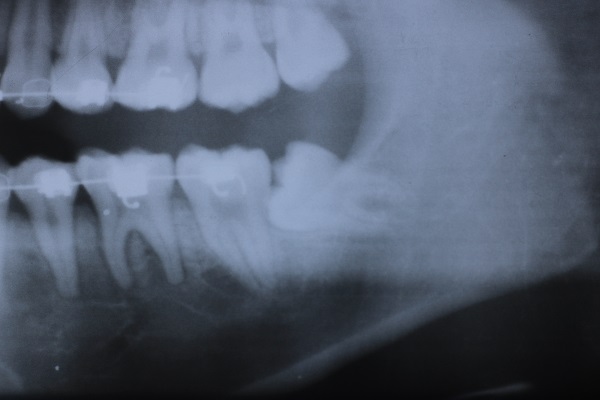

6入れ歯にしないブリッジ治療【ケース1】

H20.6.2のレントゲン

歯槽膿漏の為、上の6本の歯を抜き、上の右端から左端まで繋げたブリッジを作りました。

H31.1.25のレントゲン

H21.2.21に上の歯(ブリッジ)が完成しました。

左の写真は10年ちょっと経過したH31.1.25日に撮影した写真で、経過良好と思われます。

下顎も虫歯と歯槽膿漏のため長く持たせるために左下奥歯の一本を抜歯し残りを繋げて作りました。